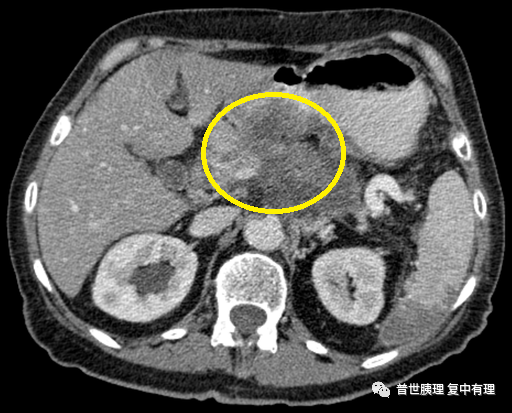

由于胰腺的位置深在,前方被肠管挡住,做彩超检查不容易发现胰体尾的占位,因为彩超最怕肠道气体的干扰,超声通常看不清楚。想要准确的筛查,胰腺癌需要做更高级的增强CT或者增强核磁共振检查,同时还要进行外周血肿瘤标记物检查。这就是为什么大多数临床医生在怀疑胰腺疾病时往往需要依赖影像学检查联合外周血肿瘤标记物检查来诊断的原因。